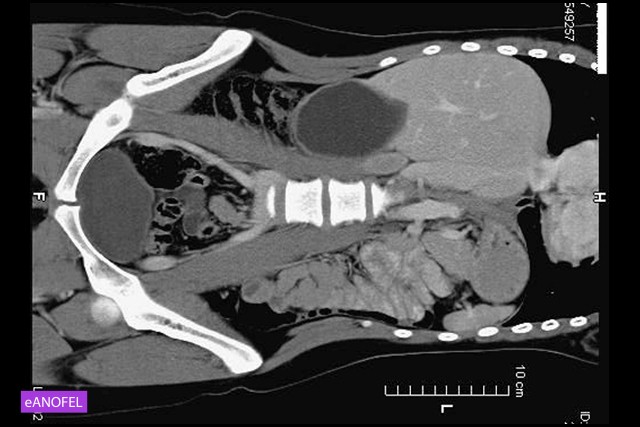

MRI – Liver cystic echinococcosis

Large hydatid cyst of the segment V of the liver displaying a thick wall and a homogenous liquid content (CL stage).